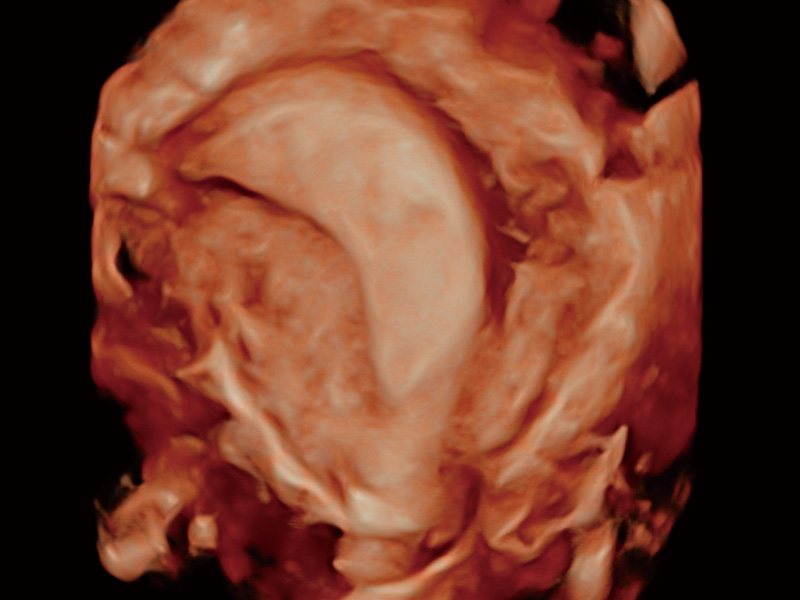

临床图

中央型宫腔粘连